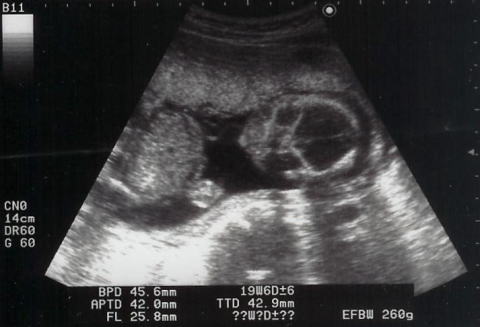

shigeruはとても元気に動いていて、心音を探すのが大変でした。エコーでは手をグーパーしながら、時々ママを見ていました。この写真は苦しそう?早く出てきたいの?でも、あと21週間はママのお腹にいてね。ママは体重が4週で1.6kg増。助産師さん・お医者様に注意されてしまいました。

必見宇宙人!?こちらを凝視してます。